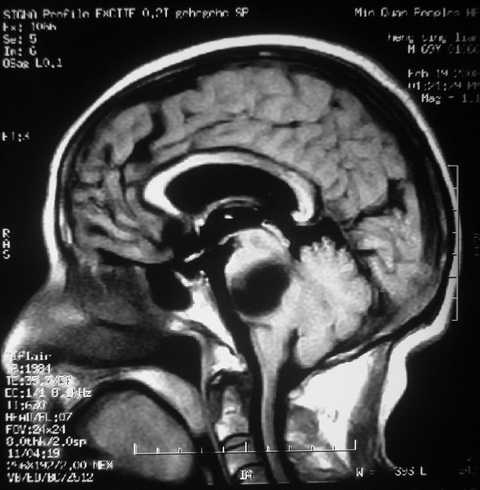

m,72,头疼,头晕两年,伴视力模糊三月,饮食呛咳两天。pe:颈部抵抗,左眼突出,左眼瞳孔约3mm,对光反射消失,双眼失明,伸舌困难,双肺呼吸音粗,心率110次/分,左上肢肌力i级,左下肢屈曲,肌张力高。现有08年2月19mri平扫及10年2月8日mri增强请会诊。ct病灶呈低密度伴散在点、片状等密度区,无明确钙化(无ct片资料可供上传)。[

脑外肿瘤,表皮样囊肿可能性大。

脑外肿瘤,囊实性,环状不规则强化,内听道扩大,考虑神经源性肿瘤

考虑表皮样囊肿。

左侧桥小脑区占位伴梗阻性脑积水----考虑 1神经鞘瘤 2室管膜瘤。

左侧桥小脑区神经鞘瘤伴梗阻性脑积水。

听神经瘤

脑外肿瘤,病灶呈匍匐蔓延,表皮样囊肿可能性大。

脑外肿瘤,病灶呈匍匐蔓延,表皮样囊肿可能性大。支持!

左侧桥脑小脑角区肿瘤并脑积水,考虑听神经瘤,脑膜瘤?

考虑听神经瘤

左侧桥脑小脑角区肿瘤并脑积水,考虑听神经瘤,